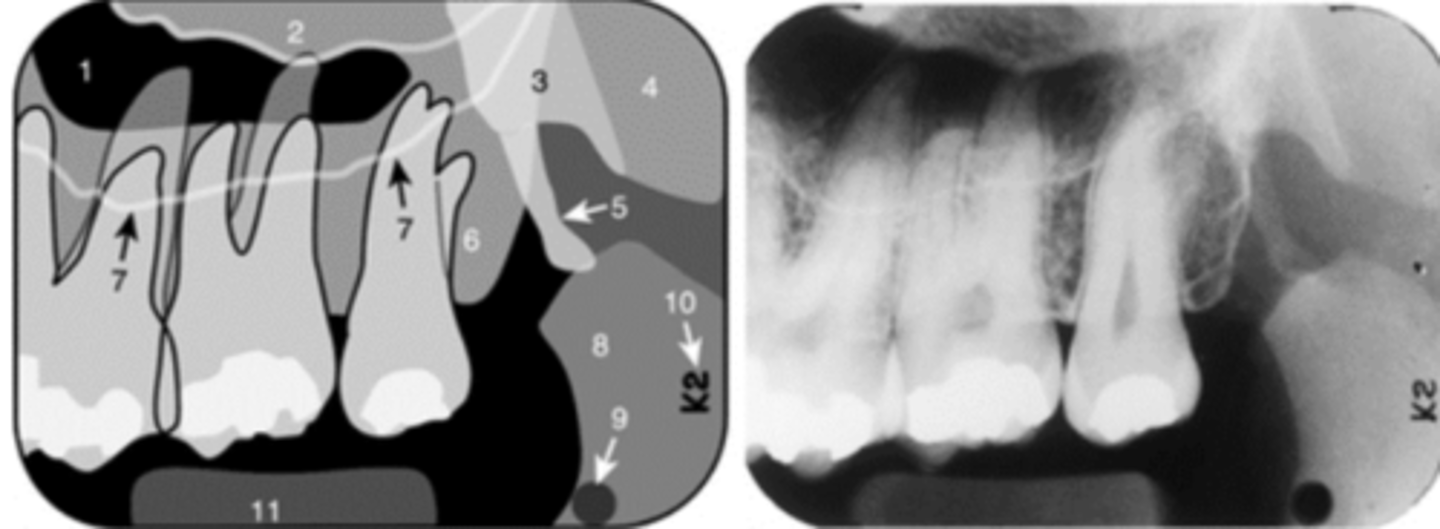

Identify the structure

<p>Identify the structure</p>

Identify both structures

<p>Identify both structures</p>

Floor of nasal cavity

6

Incisive foramen

Superior foramina of the Nasopalatine canal

10

Nose (Soft tissue)

Black arrow - Floor of the nasal cavity

White arrow- maxillary sinus

Identify the structures

<p>Identify the structures</p>

Maxillary sinus

Neurovascular canal (nutrient canal)

New cards

Septum

Zygomatic process of the maxilla

Floor of maxillary sinus

Name the curved, radiopaque line that superimposes the roots of the teeth indicated by #7.

<p>Name the curved, radiopaque line that superimposes the roots of the teeth indicated by #7.</p>

Floor of the maxillary sinus

Name the line indicated by arrows labeled #2.

<p>Name the line indicated by arrows labeled #2.</p>

Hamulus

Name the elongated radiopacity indicated by #5.

<p>Name the elongated radiopacity indicated by #5.</p>

Lateral pterygoid plate

Name the large radiopacity with a rounded inferior margin indicated by #4.

<p>Name the large radiopacity with a rounded inferior margin indicated by #4.</p>

Zygoma

Name the horizontal radiopaque line labeled #2.

<p>Name the horizontal radiopaque line labeled #2.</p>

Name the curved line scalloping between tooth roots labeled #3.

<p>Name the curved line scalloping between tooth roots labeled #3.</p>

Lip line

Name the curved radiopacity, the superior border of which is labeled #7.

<p>Name the curved radiopacity, the superior border of which is labeled #7.</p>

Name the curved, radiopaque structure indicated by the arrows.

<p>Name the curved, radiopaque structure indicated by the arrows.</p>

Sinus septum

Name the straight (slightly curved), radiopaque structure indicated by the arrows.

<p>Name the straight (slightly curved), radiopaque structure indicated by the arrows.</p>

Superior foramina of the nasopalatine duct

Name the two round radiolucencies indicated.

<p>Name the two round radiolucencies indicated.</p>

Name the curved, hyperdense line that superimposes the roots of the teeth indicated by #7.

<p>Name the curved, hyperdense line that superimposes the roots of the teeth indicated by #7.</p>

Floor of the nasal cavity

Name the line indicated by arrows labeled #1.

<p>Name the line indicated by arrows labeled #1.</p>

Inverted Y

Name the two thin, curved, radiopaque lines that merge indicated by arrows #4.

<p>Name the two thin, curved, radiopaque lines that merge indicated by arrows #4.</p>